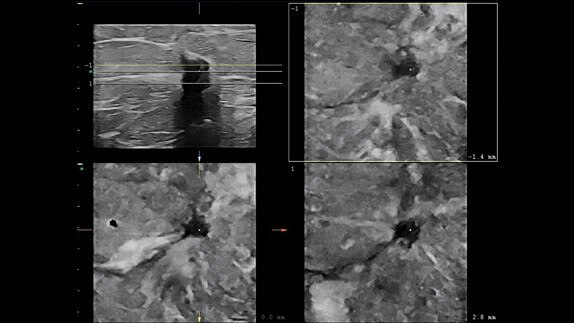

Çoklu Modaliteli Sorgulama/Alma ve ML6-15 probuyla MRG ve ultrason lezyon korelasyonu